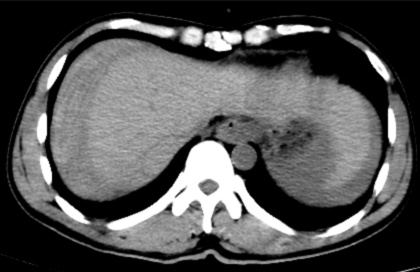

据悉,患者既往有多年乙型肝炎病史,突发右上腹剧烈疼痛入院。患者入院时血压70/40mmHg,心率110次/分,全腹压痛。血常规血红蛋白87g/L,甲胎蛋白>1210 ng/ml。腹部B超检查及CT平扫检查示“肝肿瘤并出血,腹腔积血积液”。

手术顺利,术后患者转正重症医学科给予输血、补液、止痛及康复治疗。术后3天,患者复查血,肝功能正常。后续恢复良好,并在短期内出院。